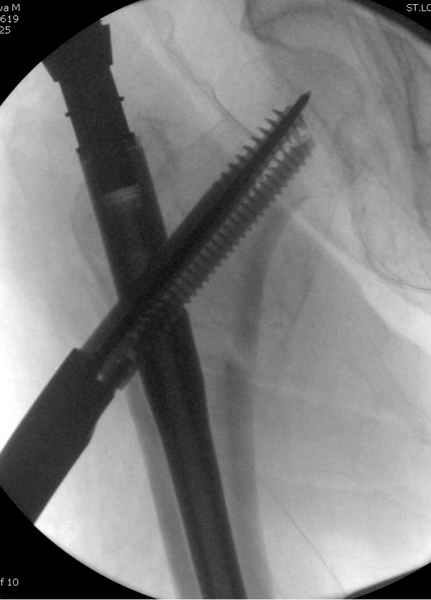

В общем, сделали. См. приложение.

Длина и из-за этого ось получились не совсем такие, как хотелось бы, все-таки срок после той операции уже 6 недель. Может быть, стоило провести дистракцию аппаратом неделю-другую. Заранее спасибо за комментарии и критику.

Наверное так и надо сделать. Будет непросто предотвратить при введении смещение Гаммы кнаружи через имеющийся дефект кортикала. Уверен, Александр Николоевич, Вы с эти справитесь. Удачи!

Александр, поздравляю от души, отличная работа, вообще-то и у меня тоже были опасения по поводу латеральной стенки. Идеальное показаниt к применению импланта закрытым методом при таких переломах, когда болт замыкается в штифте, конструкции придается угловая жесткость, примерно как в Blade Plate.

При отсутствии таких конструкций, другим альтернативным методом фиксации можно было рекомендовать короткий DHS с двумя шурупами открытым методом, а в диафиз ретроградний штифт.